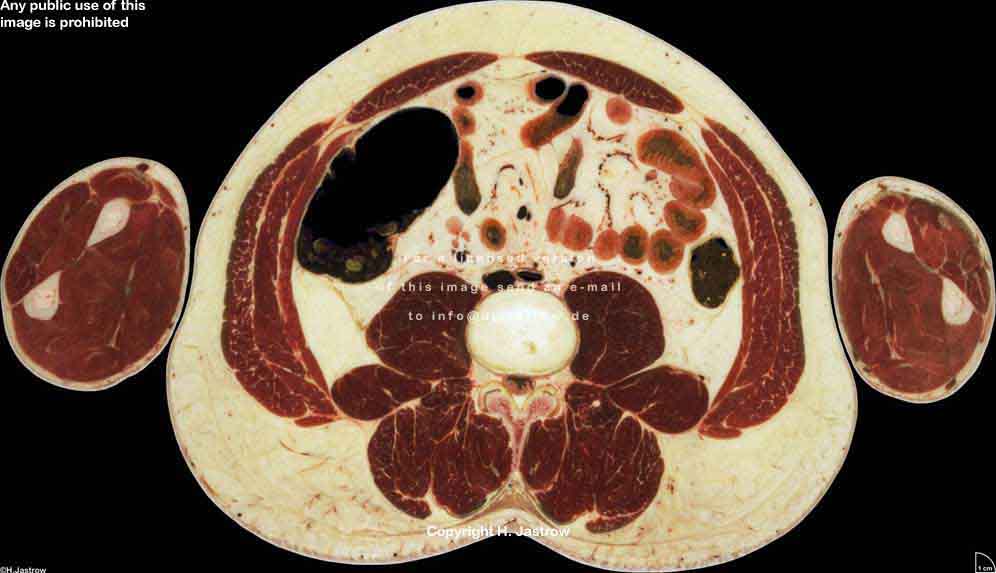

Visible Human male: Sectio transversalis 1692

CT

NMR

Pd                          / T2 \                         T1